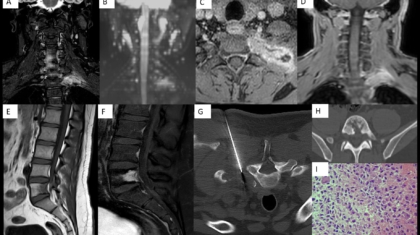

A 29-year-old man complains of neck pain extending to left side of shoulder and diffuse back pain for 5 years.